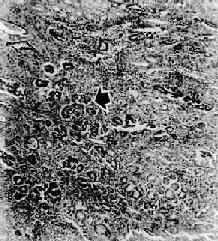

图10-18 胃硬

粘膜下层显著增生的纤维组织内有细胞浸润,细胞排成窄条索状